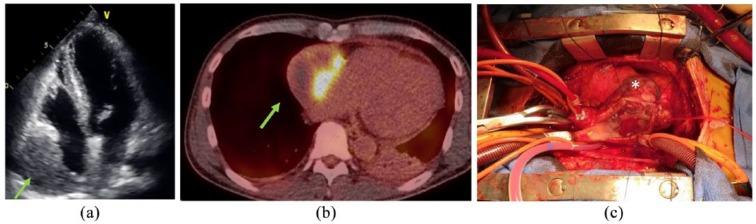

Cardiac sarcoma treatment is challenging for surgeons because of frequent tumor recurrence and poor prognosis. In addition, optimal management of recurrences is not well established. The multi-targeted tyrosine kinase inhibitor, pazopanib, was recently approved for soft-tissue sarcoma. Herein, we present a case involving recurrent cardiac angiosarcoma where the patient survived for 2 years with complete remission of disease after repeated surgical resection and treatment with oral pazopanib. Based on our experience, aggressive surgical resection combined with pazopanib may be a valid treatment for recurrent cardiac angiosarcoma to improve patient survival.

由于肿瘤频繁复发且预后不佳,心脏肉瘤的治疗对外科医生来说具有挑战性。此外,复发的最佳管理方法尚未完全确立。多靶点酪氨酸激酶抑制剂帕唑帕尼最近被批准用于软组织肉瘤。在此,我们报告一例复发性心脏血管肉瘤病例,该患者在反复手术切除并口服帕唑帕尼治疗后,疾病完全缓解,存活了2年。根据我们的经验,积极的手术切除联合帕唑帕尼可能是复发性心脏血管肉瘤的有效治疗方法,可提高患者生存率。